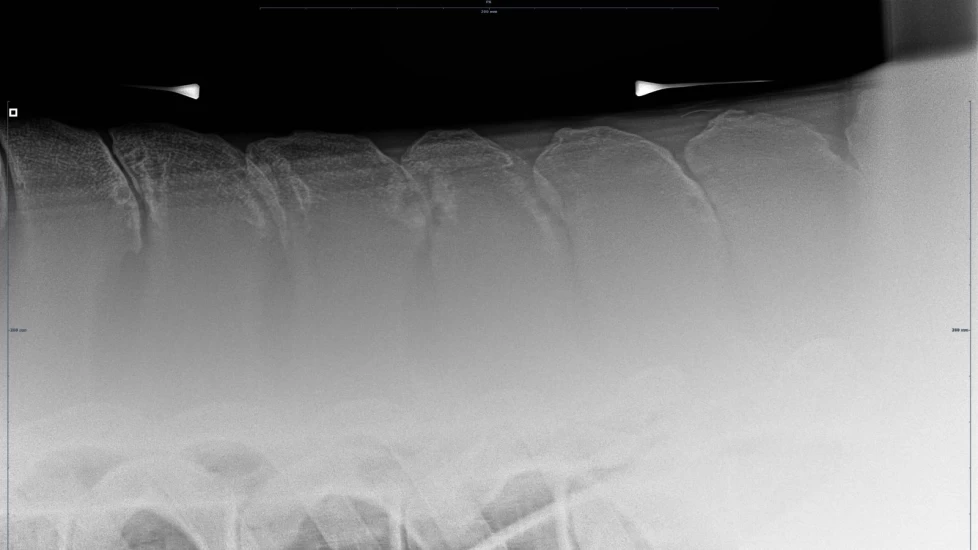

Det er flere årsaker til at hester utvikler kissing spines, men det finnes råd om behandling. Foto: Privat

Hesten har ryggvirvler som alle har torntapper (Dorsal spinous processes), og hestens rygg består av 18 brystvirvler (thorakalvirvler) og seks lendevirvler (lumbalvirvler). De har et naturlig mellomrom mellom hverandre på fem til syv millimeter.